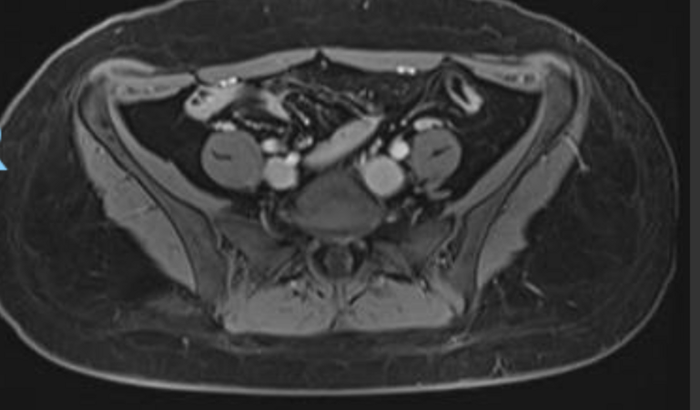

Eu sou Ana Beatriz, 32 anos, Carioca, mãe do Davi de 15 anos. A 1 mês descobri um tumor borderline, e desde então tenho tentado pelo sus a remoção deste tumor no ovário esquerdo, pois é indicado a cirurgia devido o crescimento rápido desse tumor e a preocupação dos órgão que ele está comprimindo. Devido a demora no SUS, terei que fazer particular, e o total hoje é R$20.800,00, podendo ultrapassar caso na Biópsia na hora da cirurgia, seja constatado malignidade. Constatado benignidade, a cirurgia se encerra e somente o pós operatório fica. Saúde não se mede em real, mas é uma surpresa de repente, que você não tem opção de não fazer. Deus abençoe sua vida, e sua contribuição.